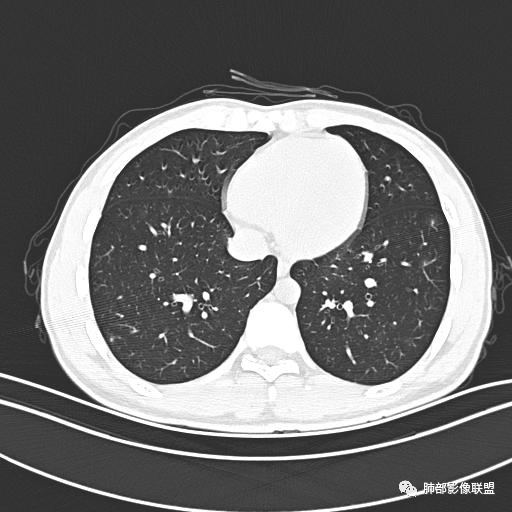

【每日晨读】年轻男性,发热+皮疹+肺内点晕

主  诉:发热、全身皮疹2天。

现病史:患者源于2天前受凉后出现发热,最高体温为38.5℃,且颜面部出现少量皮疹,无鼻塞、流涕、咳嗽、咳痰,未在意而未作特殊处理,次日全身皮疹逐渐增多至全身,伴轻度瘙痒,在当地卫生所给予抗病毒、抗感染治疗(具体用药不详)体温有所下降,但皮疹无明显消退,无腹痛、头痛,食欲无明显减退,为进一步诊治,遂于今日急来我院求治,患者目前精神尚可,体力正常,食欲正常,睡眠正常,体重无明显变化,大便正常,排尿正常。

小强:青年,发热,皮疹;双肺散在结节,周围磨玻璃,点晕征,疱疹病毒感染,鉴别荚膜组织胞浆菌,结核。 大雄:青年,急性起病,发热伴全身皮疹2天,抗病毒治疗体温有下降。双肺随机分布大小不等类圆结节,“点晕征”。考虑水痘-疱疹病毒(VZV)血播询问接触史,查体皮疹分布以及形态基本可诊断。 王开金江津中心医院呼吸科:青年男性,起病急,病程短,以发热,皮疹为首发症状,感染指标以单核细胞升高为主,胸部ct双肺多发结界,周围有晕,点晕表现,随机分布,同意於老师意见,水痘疱疹病毒血流感染累及肺。 王秀仙:双肺多发大小不等结节,周围有晕,边缘模糊,呈点晕征表现。青年,急性起病,发热伴全身皮疹2天,抗病毒治疗体温有下降。考虑疱疹病毒。鉴别荚膜组织胞浆菌。 傅昌瑜:19岁男性,发热、全身皮疹2天,单核细胞增高,双肺多发结节,结节边缘见边界不清磨玻璃影。点晕征+发热、全身皮疹+单核细胞增高——考虑水痘-带状疱疹病毒肺炎。 一切∮随缘:年轻男性,发热,皮疹两天,实验室,CRP,PCT增高,影像:双肺多发散在磨玻璃结节,边界欠清,大小不等,呈点晕征改变,以血管束周围分布为主,局部血管束略增粗,其它无明显改变,考虑:1:病毒性肺炎(水痘疱疹病毒?不知道皮肤有无改变)2:真菌(组织胞浆菌,血管侵袭性肺曲霉)3:GPA4:寄生虫(实验室没有看到嗜酸细胞增高) 赵山河:双肺散在结节,周围有晕,边缘模糊,呈点晕征表现。青年,急性起病,发热伴全身皮疹2天,抗病毒治疗体温有下降。考虑水痘—疱疹病毒感染。洪桥爱:青年男性,发热、皮疹2天,伴瘙痒,皮疹于面部首发,之后进展至全身,虽然没有对皮疹进行描述,但是从出疹时间及皮疹进展情况,伴瘙痒,应该就是个水痘患者;CT提示双肺随机分布结节影,部分结节伴有边界不清晕征,考虑水痘血播肺。 刘强:年轻男性,急性起病,皮疹,发热,抗感染治疗体温下降,说明有效。影像表现为散在点晕征,感染类疾病谱(疱疹病毒,真菌,结核),结合年龄,皮肤皮疹,考虑水痘-疱疹病毒性肺炎。 小兜:男性,19岁,发热皮疹两天,颜面部至全身,CRP,降钙素及单核增高。CT示双肺散在小结节,周围伴磨玻璃影,点晕征,考虑为水痘-带状疱疹病毒(varicella-zoster virus,VZV)肺炎 必有路:青年,皮疹+发热+“点晕征”→水痘-疱疹病毒(VZV) 许慧良:青年男性患者,发热、皮疹2天,体温最高38.5℃,第3天皮疹扩展至全身,伴瘙痒,胸部CT:双肺多发随机分布的小结节,结节周边见边界模糊的晕征,考虑水痘病毒感染流心明智:男,19,急性起病,发热伴全身皮疹2天。出疹顺序头→全身,抗病毒有效。胸部CT:两肺多发大小不等类圆形实性小结节影,随机分布,结节周围环绕GGO,边界模糊,呈点晕征。出疹特点是关键,未提示。考虑:血播病毒性肺炎,水痘-疱疹病毒?麻疹?鉴别荚膜组织胞浆菌、TB、血管炎、寄生虫等。 浪迹天涯:病灶多为5-10mm大小结节,结节周围可见磨玻璃样的晕环,常多发,可分布于肺内任何区域,考虑水痘—带状疱疹病肺炎如果短时间内有新的一个区域浸润,更加能说明,